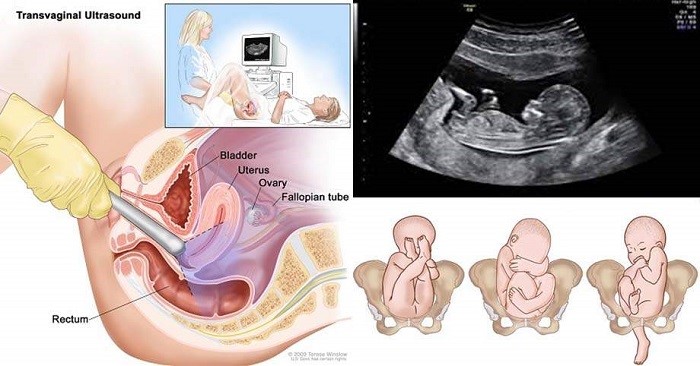

Siêu âm đầu dò là gì?

Siêu âm đầu dò có lẽ là 1 loại siêu âm không còn quá xa lạ với chị em phụ nữ. Nhất là với các bạn đã từng đi khám phụ khoa. Siêu âm đầu là loại siêu âm cực kì quan trọng, trong những tháng đầu mang thai.

Siêu âm đầu dò giúp bác sĩ kiểm tra được vị trí thai đã vào tử cung hay chưa, mẹ đã mang thai hay chưa, chuẩn đoán mang thai vào giai đoạn sớm nhất có thể. Vì những lần đầu tiên mang thai mẹ được bác sĩ thực hiện siêu âm đầu dò.

Nên khi thai nhi đã phát triển nhiều mẹ sẽ thắc mắc: Thai 12 tuần siêu âm bụng hay đầu dò? vì các mẹ đều rất mong ngóng nhìn thấy hình hài của con. Thông thường vào tuần tuổi thứ 12 các bác sĩ sẽ thực hiện siêu âm bụng. Như vậy, mẹ có thể được nhìn thấy những hình ảnh rõ ràng nhất của thai nhi

Vào tuần tuổi thứ 12, phần lớn bác sĩ sẽ chỉ định cho mẹ siêu âm bụng 3D hoặc siêu âm 4D. Các dạng siêu âm này sẽ giúp bác sĩ nhìn rõ nhất và kiểm tra rõ nhất các dấu hiệu bất thường (nếu có) của thai nhi.

Tuy nhiên, với câu hỏi: Thai 12 tuần tuổi siêu âm bụng hay đầu giò thì đáp án là nên siêu âm bụng. Vì ở tuần thứ 12 khi thai nhi đã nặng khoảng 15g và có chiều dài tầm 5.5 cm. Thì các bác sĩ đã có thể nhìn được khá rõ hình thể của thai nhi cũng như bắt đầu xem được vùng da gáy.

Ở giai đoạn phát triển này, siêu âm bụng 3D hay 4D là cách tốt nhất giúp bác sĩ chẩn đoán dị tật, đột biến nhiễm sắc thể, dị tật cơ hoành,.. Thai nhi dù còn rất nhỏ nhưng đã hình thành khá nhiều bộ phận như: ngón tách tách dần, xương cứng cáp, có tim thai đập nhanh, ruột phát triển,…